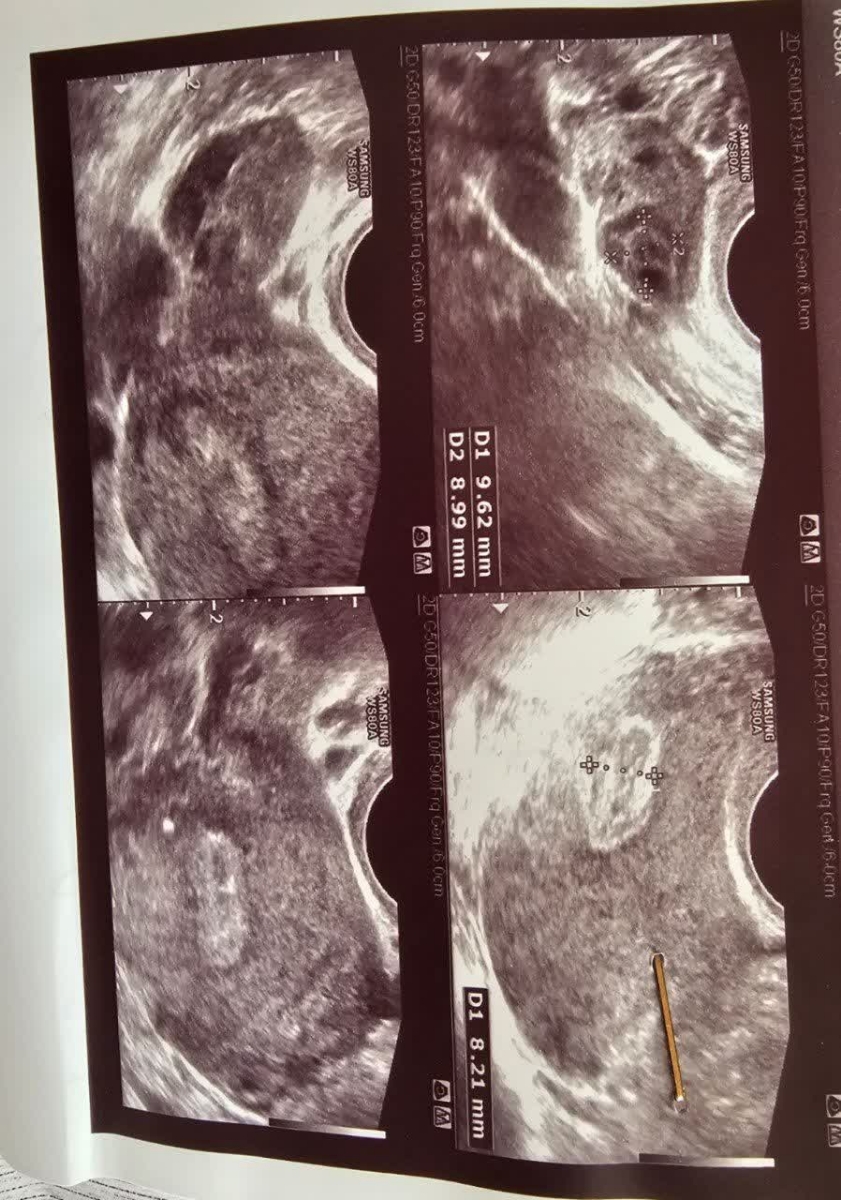

اینم سونوم

بهش گفتم برای خارج رحمی گفت من چیزی نمیبینم فعلا باید زیر نظر باشی بعدا دوباره چک کنی یا تیتر یا سونو رو

گفت داخل رحمت لخته های خون هست احتمالا سقط شده